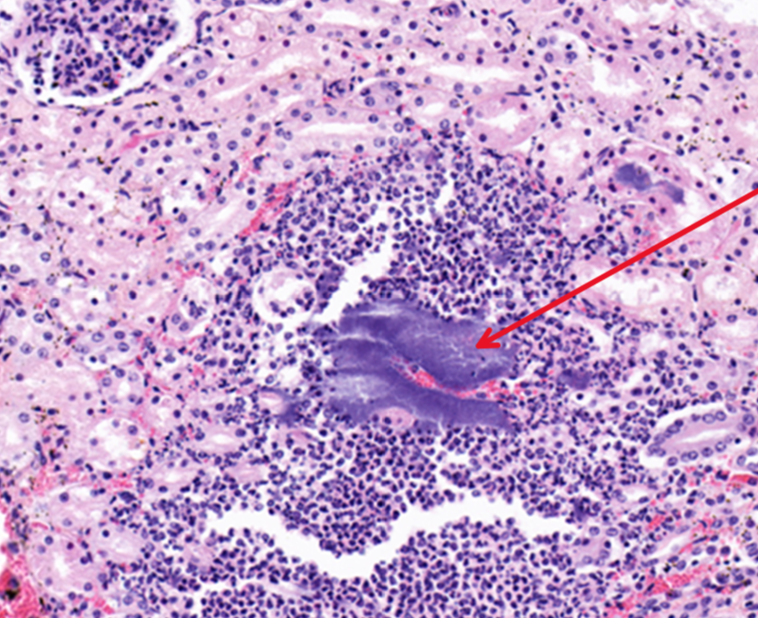

What are these cells and what does this imply about the duration?

A

neutrophils which suggests acute inflammation

There are bacterial colonies trapped and proliferating within the capillaries, are they post mortem or are they important in the pathogenesis of the lesions?

they are likely antemortem bacteria because they are surrounded by an inflammatory response

Q

What would the morphologic diagnosis for this lesion?

acute purulent glomerulonephritis with bacterial colonies

Identify this structure:

bacterial colonies